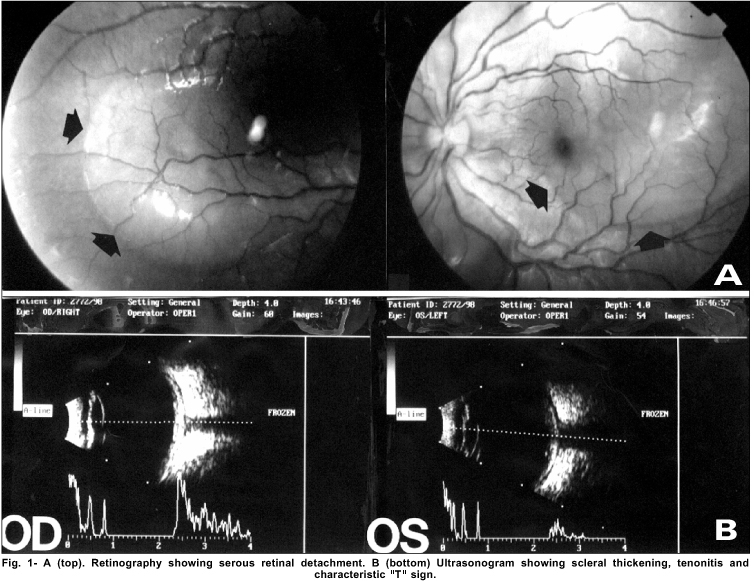

The ocular examination revealed a bilateral proptosis and the corrected visual acuity was 0.6 in the right eye and 0.1 in the left eye. Intraocular pressure and biomicroscopy were normal. Pupillary reflexes were slightly decreased in both eyes. Fundoscopy revealed bilateral serous retinal detachment in the posterior pole ( Figure 1A).

An elevated (65 mm) first-hour sedimentation rate was observed. Ultrasound ( Figure 1B) and the angiofluoresceinography confirmed the diagnosis of bilateral posterior scleritis.